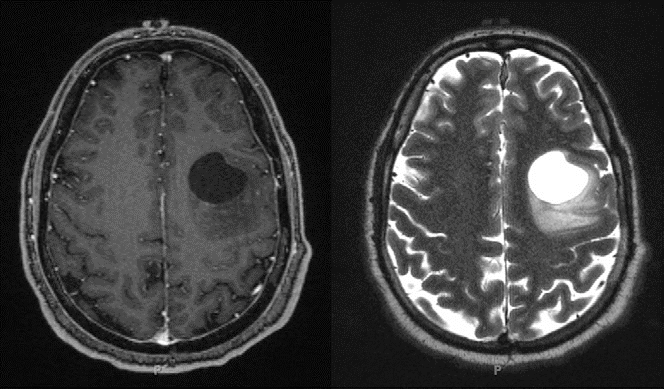

Our patient had normal laboratory values. A dedicated EEG done after the continuous positive airway pressure titration study was also normal. MRI revealed the presence of a prominent left frontal lobe mass with a large cystic component and peripheral nodular and patchy enhancement, suggesting a high-grade glial tumor (Figure 2). Although the overall incidence of seizure decreases in middle age, the proportion due to tumor increases in this age group (10).

Figure 2. Brain MRI obtained shortly after the patient’s continuous positive airway pressure titration study. The patient was found to have a circumscribed cystic mass in the left middle frontal gyrus. Left panel: T1-weighted image postcontrast. Right panel: T2-weighted image.